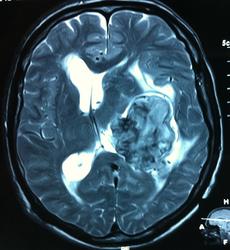

Начало вот здесь http://www.radiomed.ru/cases/kt-gms-obemnoe-obrazovanie-levoi-gemisfery-bolshogo-mozga-vnutrizheludochkovaya-meningioma. Пациент оперирован (меня сначала дезинформировали по поводу операции), перед операцией состояние ухудшилось, возникла правосторонняя гемиплегия, которая осталась и после декомпрессии. МРТ, КТ снимки и выписку предоставила супруга пациента, снимал на iphone, простите за качество, дисков с исследованиями не записывали. Надеюсь вопрос по данному случаю исчерпан.

Т2

FLAIR

И Вы считаете, что эта опухоль имеет интравентрикулярную локализацию?

Изначально по КТ я так предпологал, а теперь на 100% уверен, разве МРТ это не показало? Гистологически - менингиома, опухоль мозговой оболочки. Покажите, пожалуйста, образование где-нибудь прилежит к костям, где есть мозговая оболочка? Я не вижу, зато отчетливо вижу в левом боковом желудочке из оболочек сосудистого сплетения. Что вас еще смущает? По-моему, предостаточно фактов, чтобы развеять все сомнения.

Мне видится так. Иначе в данной локализации просто неоткуда расти оболочечной опухоли. На контрольной КТ, после декомпрессии, когда срединные структуры стали действительно срединны, правое обызвествленное сосудистое сплетение видно отчетливо, а левое, где оно? Ведь если бы образование компремировало, то после операции, когда часть мозга пролабировало в трепанационное отверстие мы бы увидели и левое сосудистое сплетение, но оно интимно связано с образованием и даже "потянулось" за ним в сторону декомпрессионного отверстия, потому что это и есть "росток" откуда выросла опухоль.